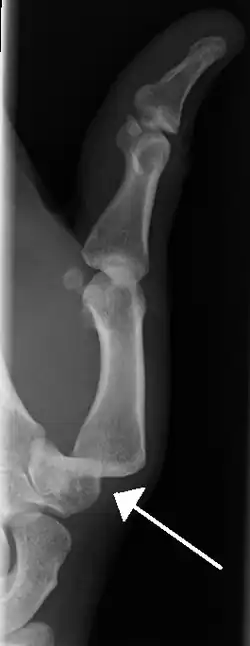

Dislocation of the carpo-metacarpal joint.

Radiograph of right fifth phalanx dislocation resulting from bicycle accident -

Right fifth phalanx dislocation resulting from bicycle accident